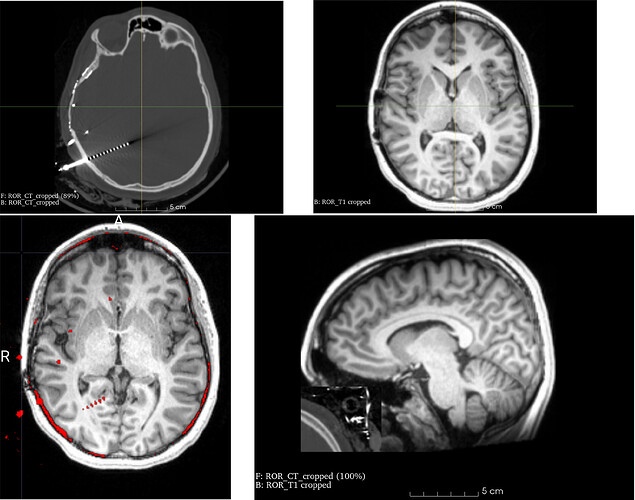

Plase see screenshow below. I would like to overlay preoperative T1 MRI (top left) with postoperative CT (top right). Images have already been co-registered in SPM, and alignment looks great in MRICrogl (bottom left). For some reason, the two images look completely out of place with each other in 3D slicer (I tried cropping out unnecessary volume too, but with no sucsess). Any help would be greatly appreciated!